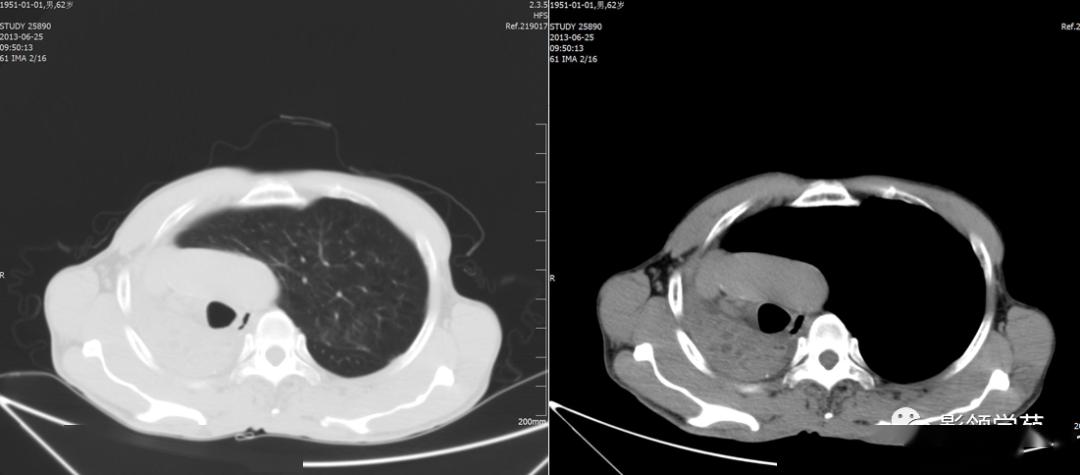

两下肺盘状肺不张(红箭头)两下肺圆形或椭圆形密度增高影;(黄箭头)

图片尺寸1080x540